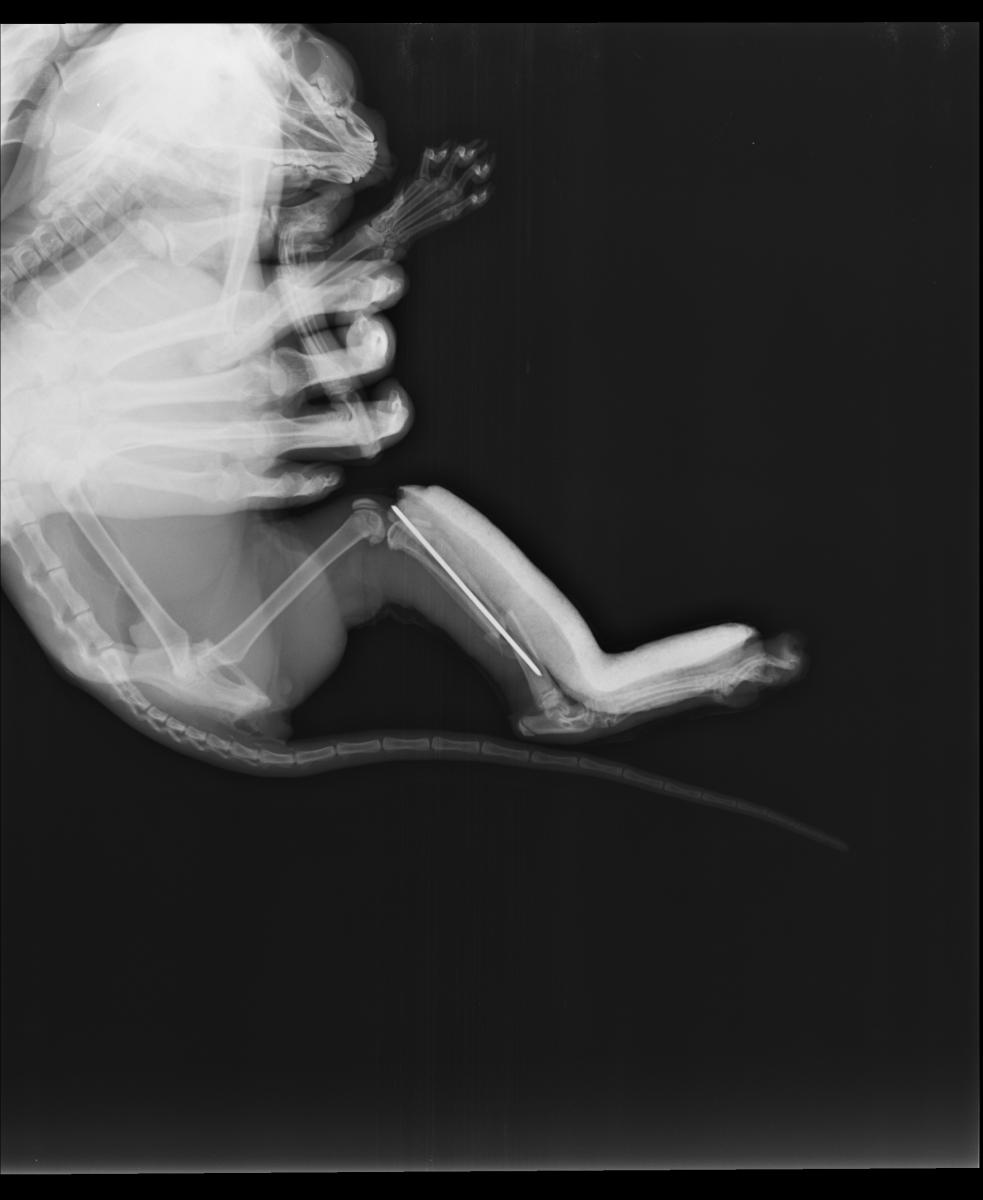

Судя по снимку, кошке однозначно показана операция.

Врач сообщил, что при таком характере перелома, как на снимке выше, остеосинтез желательно проводить накостными пластинами. Он же сказал, что в Подольске с пластинами никто не работает.

Другой врач высказал сомнение в возможности использования пластин из-за миниатюрных размеров кости.

Вкратце: операцию провели, от наркоза кошка отходила очень долго и громко. Наверное в это время и сместила немного кость. Вот снимки через два дня после операции.

История закончилась хорошо. Кость срослась, спица в ней никак не мешает движению и не дала осложнений.

На снимке - состояние через 80 дней после операции.

Хочу отметить, что в Подольске все клиники используют только метод остеосинтеза спицами. Если перелом со множеством осколков, то фиксировать их лучше другими методами, то есть придётся везти животное в клинику в другой город.